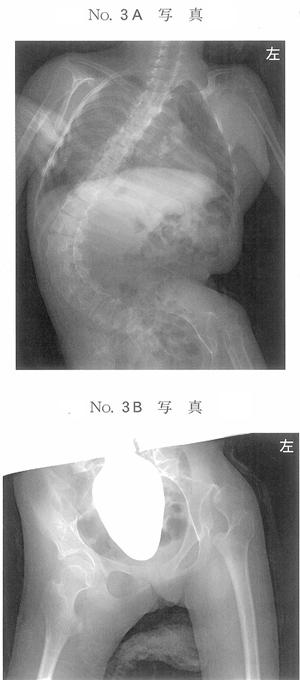

14歳の女子。痙直型四肢麻痺によって座位保持ができず座位保持装置を使用している。最近側弯が増強したため外来を受診した。脊椎エックス線単純正面像(別冊No. 3A)と骨盤エックス線単純正面像(別冊No. 3B)とを別に示す。座位姿勢を改善させる方法で適切でないのはどれか。